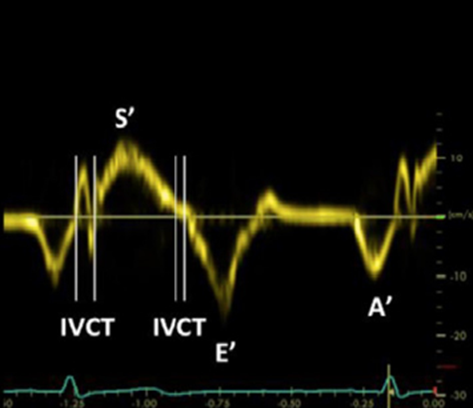

Evaluating RV Function

Detecting reduced RV function or strain is a key component of the quantitative evaluation. The two methods described here both evaluate the systolic movement of the tricuspid valve annulus at the RV free wall in the A4C view. This movement is considered a surrogate for contractility of the RV. The first method of evaluating RV strain is tissue doppler imaging (TDI). With an A4C view, the TDI doppler gate is placed in the tissue of the lateral tricuspid annulus, then a tracing generated. (Figure 4) The positive deflection, which represents maximum annular velocity, is referred to as s’. If s’ is less than 9.5, there should be concern for RV strain.

Figure 4. TDI of tricuspid annulus for evaluation of RV strain.